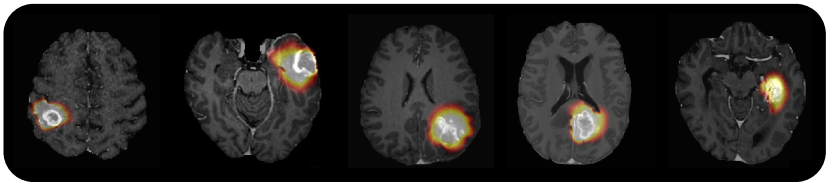

Refer to caption

Figure 4: Qualitative examples of the tumor simulations obtained from our proposed pipeline. The brain images correspond to five different patients.